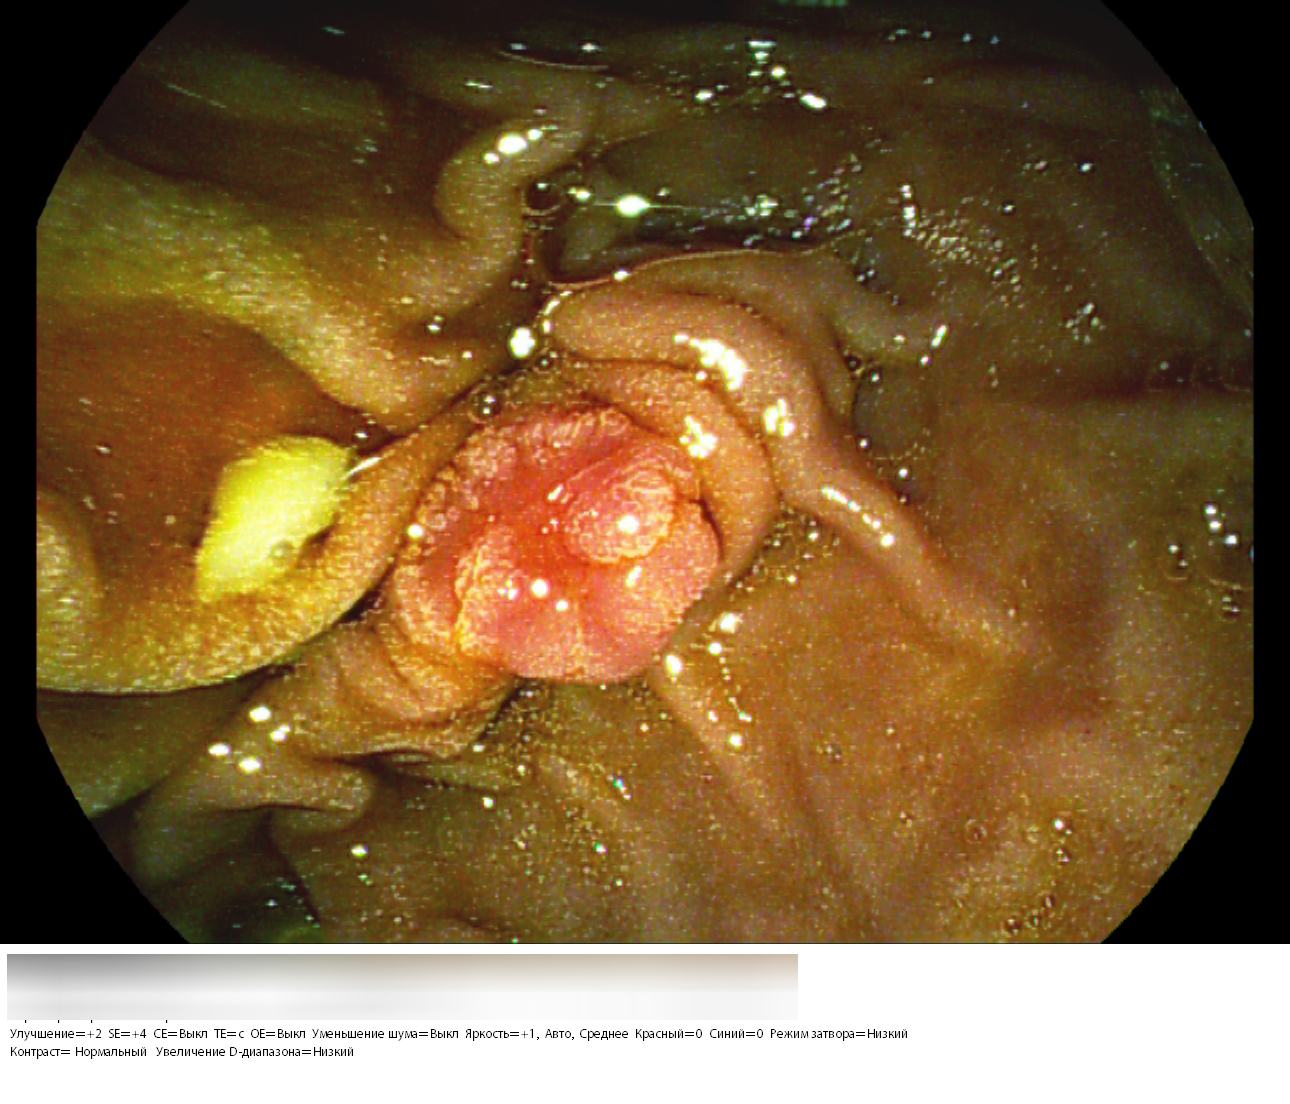

Կատարված հետազոտությունների արդյունքում ախտորոշվել է ֆատերյան պտիկի վիլլոտուբուլյար ադենոմա։

Ուռուցքաբանության ազգային կենտրոն դիմելուց 4 օր անց 58 ամյա տղամարդում կատարվել է էնդոսկոպիկ ամենաբարդ վիրահատություններից մեկը։ Ընդհանուր անզգայացման պայմաններում կատարվել է ամպուլէկտոմիա, պանկրեատիկ ծորանի և ընդհանուր լեղածորանի ստենտավորում։ Այսպիսի վիրահատությունը համարվում է էնդոսկոպիայի ոլորտում ամենաբարդերից մեկը։